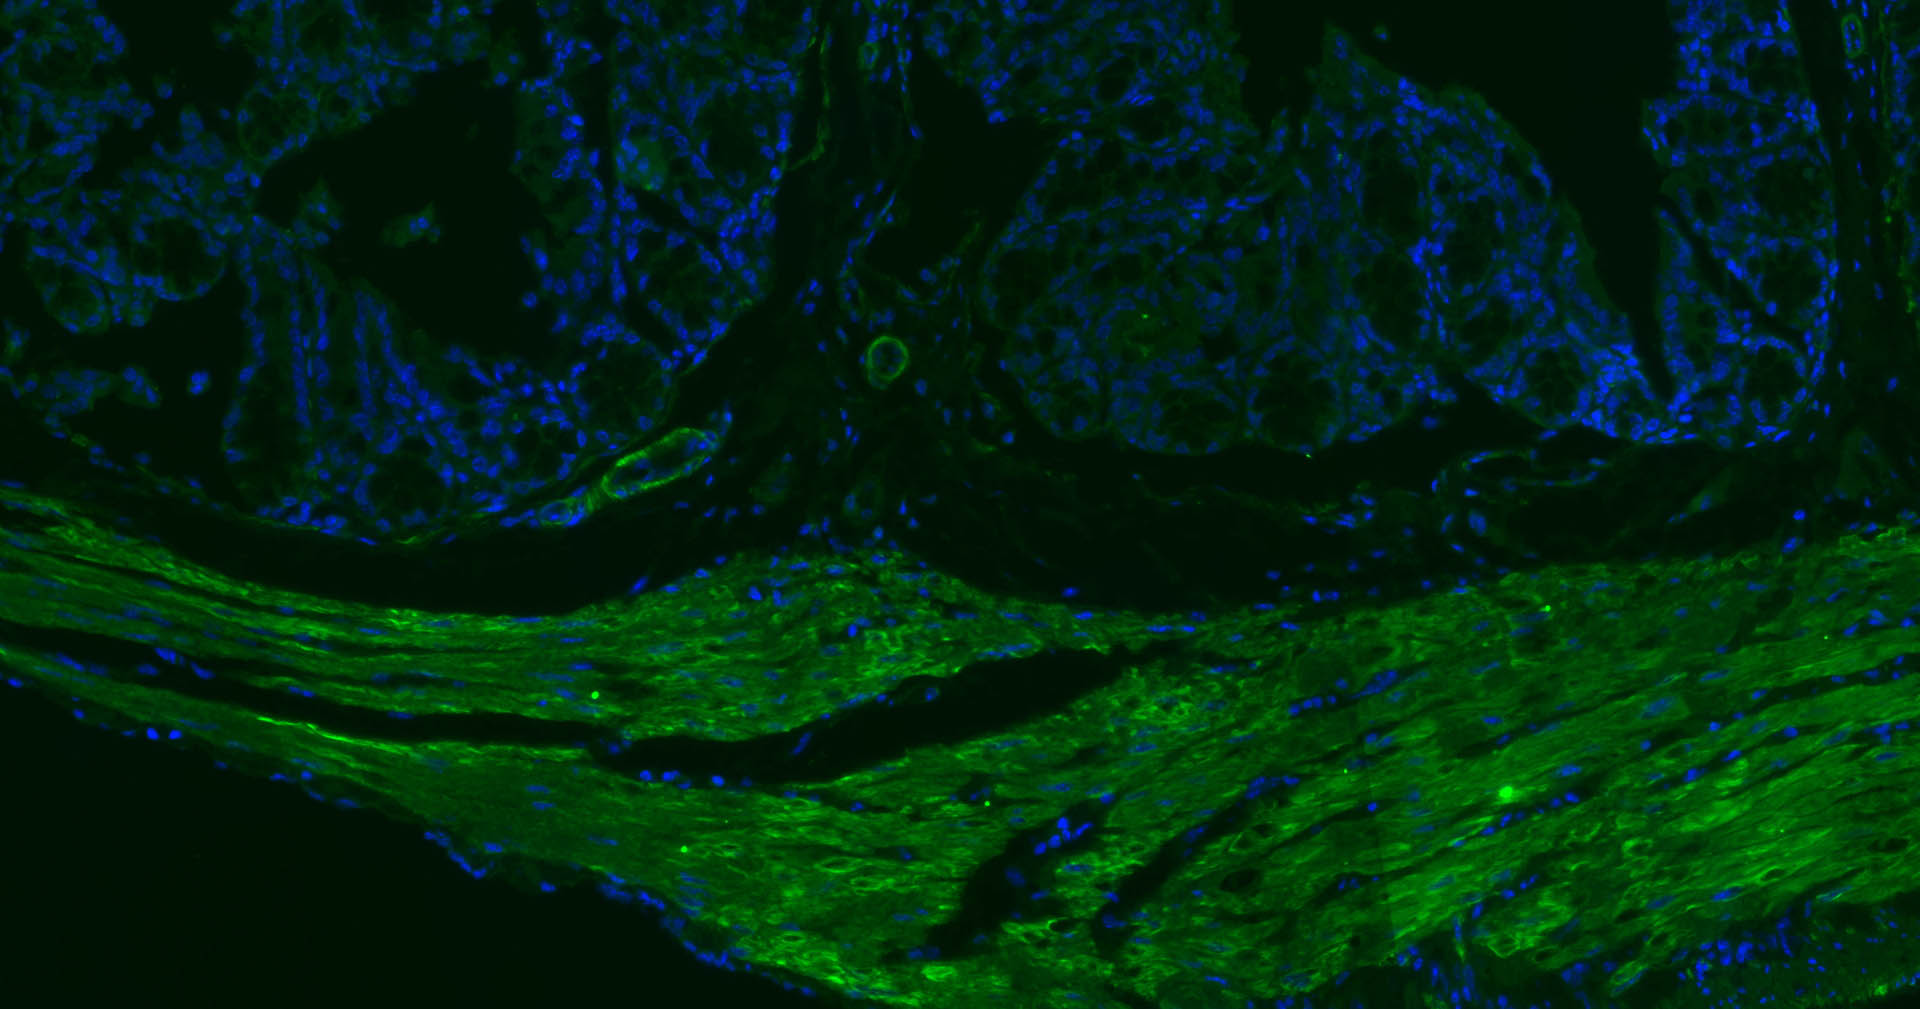

Paraformaldehyde-fixed, paraffin embedded Rat Colon; Antigen retrieval by boiling in sodium citrate buffer (pH6.0) for 15 min; Incubation: alpha smooth muscle Actin/BF488 Antibody, conjugated (bsm-33187M-BF488) at 1:100 overnight at 4°C; DAPI (blue, C02-04002) was used to stain the cell nuclei.

Paraformaldehyde-fixed, paraffin embedded Mouse Colon; Antigen retrieval by boiling in sodium citrate buffer (pH6.0) for 15 min; Incubation: alpha smooth muscle Actin/BF488 Antibody, conjugated (bsm-33187M-BF488) at 1:100 overnight at 4°C; DAPI (blue, C02-04002) was used to stain the cell nuclei.